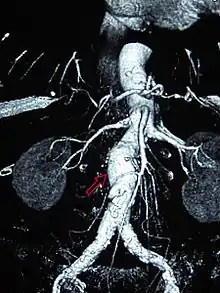

Abdominal aortic aneurysm

Abdominal aortic aneurysms (AAAs) are more common than their thoracic counterpart. One reason for this is that elastin, the principal load-bearing protein present in the wall of the aorta, is reduced in the abdominal aorta as compared to the thoracic aorta. Another is that the abdominal aorta does not possess vasa vasorum, the nutrient-supplying blood vessels within the wall of the aorta. Most AAA are true aneurysms that involve all three layers (tunica intima, tunica media and tunica adventitia). The prevalence of AAAs increases with age, with an average age of 65–70 at the time of diagnosis. AAAs have been attributed to atherosclerosis, though other factors are involved in their formation.[7]

The risk of rupture of an AAA is related to its diameter; once the aneurysm reaches about 5 cm, the yearly risk of rupture may exceed the risks of surgical repair for an average-risk patient. Rupture risk is also related to shape; so-called "fusiform" (long) aneurysms are considered less rupture-prone than "saccular" (shorter, bulbous) aneurysms, the latter having more wall tension in a particular location in the aneurysm wall.[9]

Before rupture, an AAA may present as a large, pulsatile mass above the umbilicus. A bruit may be heard from the turbulent flow in the aneurysm. Rupture may be the first sign of AAA. Once an aneurysm has ruptured, it presents with classic symptoms of abdominal pain which is severe, constant, and radiating to the back.[9]

The diagnosis of an abdominal aortic aneurysm can be confirmed by the use of ultrasound. Rupture may be indicated by the presence of free fluid in the abdomen. A contrast-enhanced abdominal CT scan is the best test to diagnose an AAA and guide treatment options.[10]